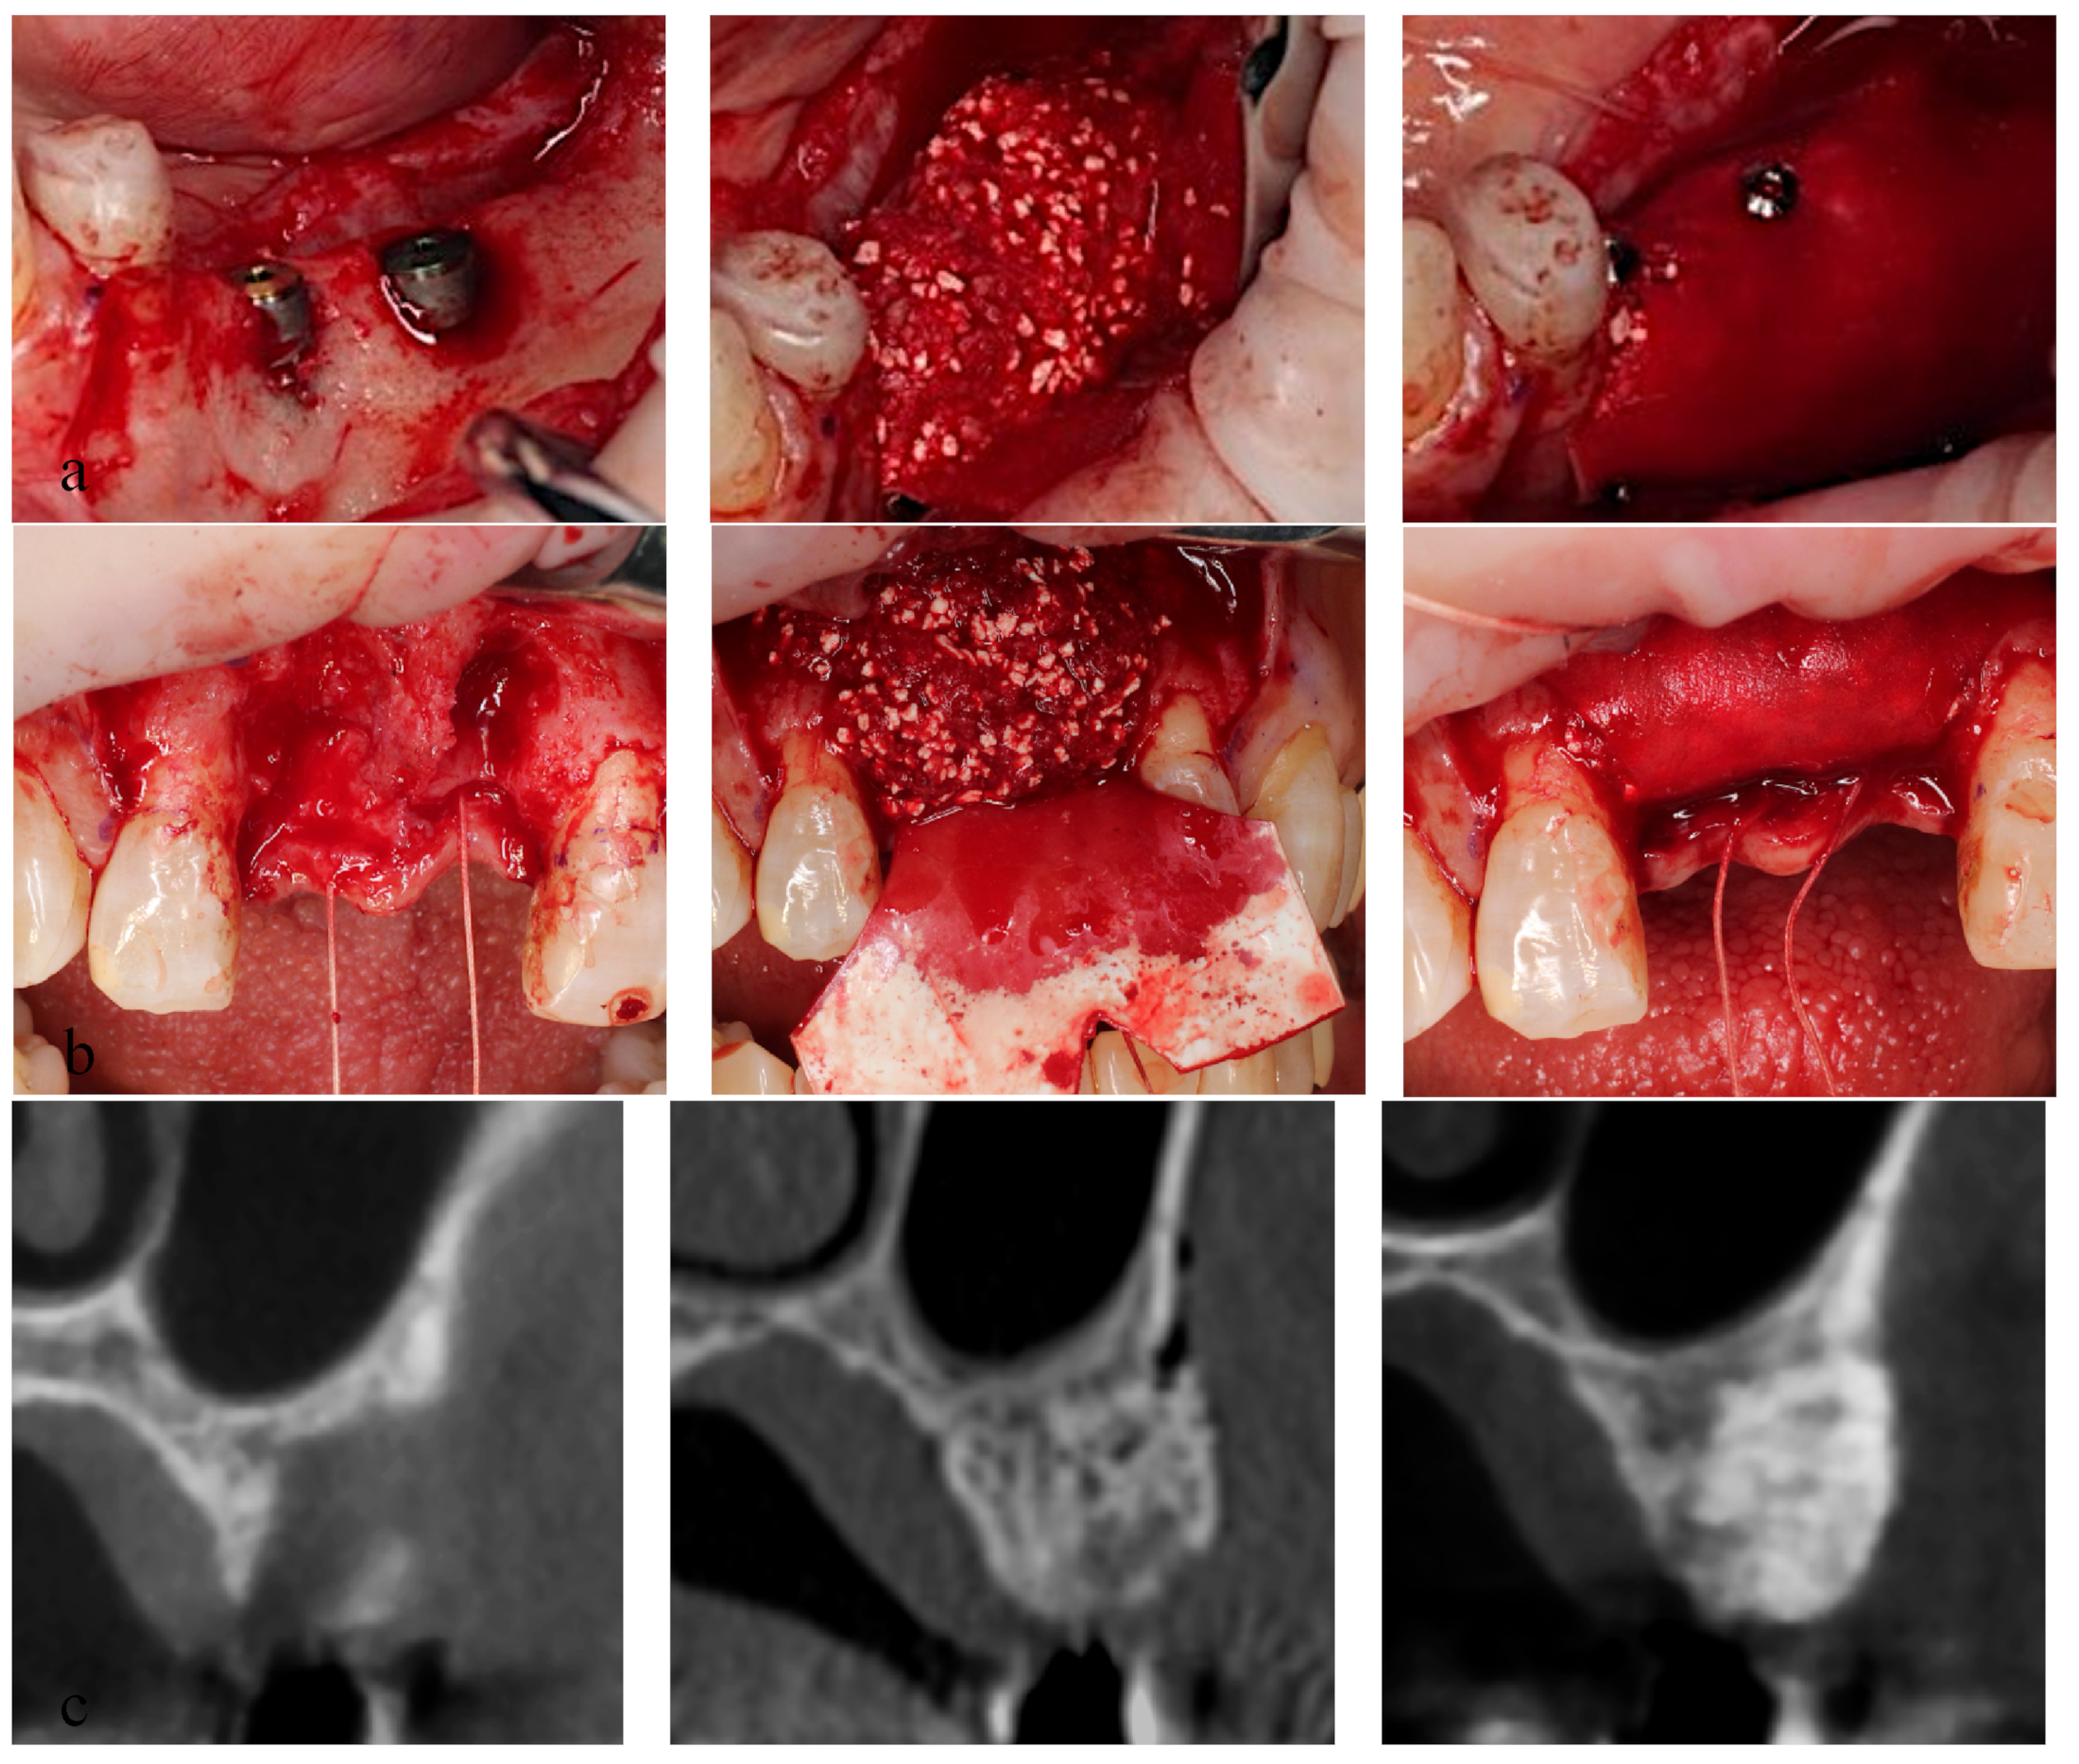

2.1. Surgical Procedures (Figure 2)

- Groups A and B: The mucoperiosteal flap was elevated and alveolar bone atrophy or defects were observed. Following implant placement using a surgical guide, the exposed implant region was covered with a bone graft material mixture, and the materials were enveloped by the GBR membrane. The GBR membrane was fixed with tuck pins (tru TACK®, ACE surgical, AZ, USA) to maintain the graft materials at the place in group B but not in group A. After a tension-reducing periosteal incision was made, the wound was closed without tension.

- Group C: Bone augmentation was performed as in group B but without implant placement.

- Bone augmentation using GBR was performed simultaneously with implant insertion in groups A and B.

- Bone augmentation by GBR was performed prior to implant insertion in group C.

- CT images of group C (before, left, right, middle, and 150 days after GBR; right).